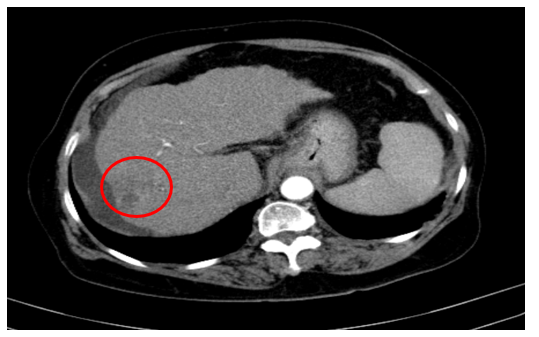

Chụp cắt lớp vi tính ổ bụng

Gan: biến đổi hình thái, phì đại HPT I, bờ gan không đều. Nhu mô gan phải có khối giảm tỉ trọng hình chêm kích thước 37x35mm, ranh giới không rõ, co kéo bao gan lân cận, trong có phần tăng tỉ trọng của vật liệu nút mạch, ngấm thuốc kém sau tiêm. Dịch quanh gan 33mm. Dịch tự do ổ bụng

Hình ảnh u gan phải sau điều trị hiện không thấy phần ngấm thuốc sau tiêm (Bệnh đáp ứng điều trị nên không có tổ chức ngấm thuốc) (Vòng tròn đỏ)